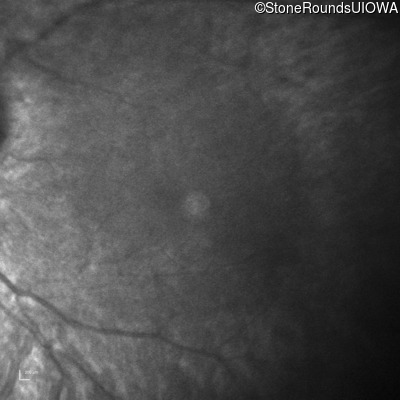

Infrared Fundus Photograph - Right -

No Light Perception

Exemplar

Expanded OCT Stack

×